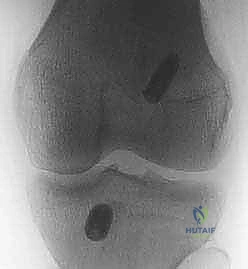

- الأشعة السينية (X-rays): تُطلب أولاً لنفي وجود أي كسور عظمية مصاحبة، مثل كسر "سيجوند" (Segond Fracture) وهو كسر قلعي صغير في الجانب الخارجي للقصبة يُعتبر علامة شبه مؤكدة لتمزق الرباط الصليبي.